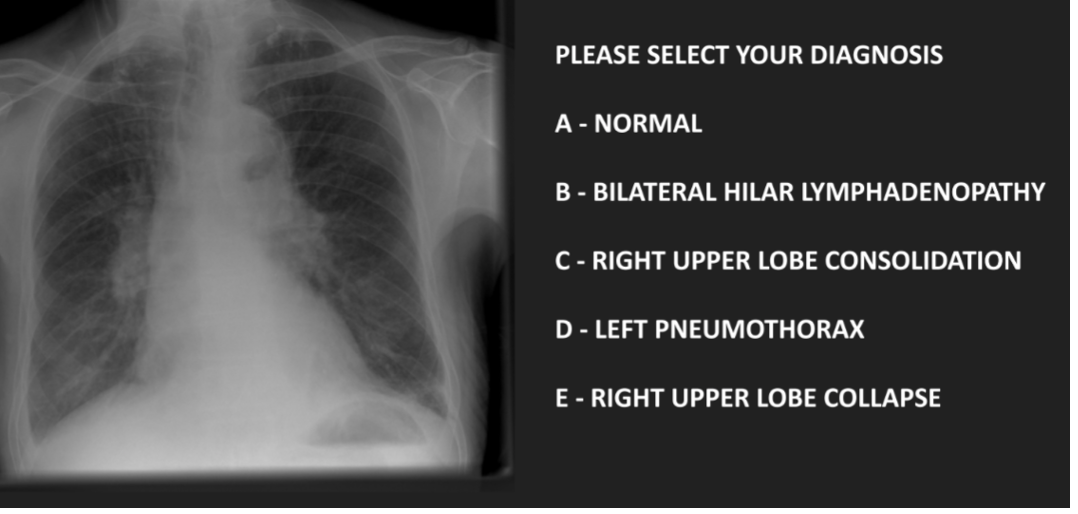

Q

diagnosed

A

C- right upper lobe collapse